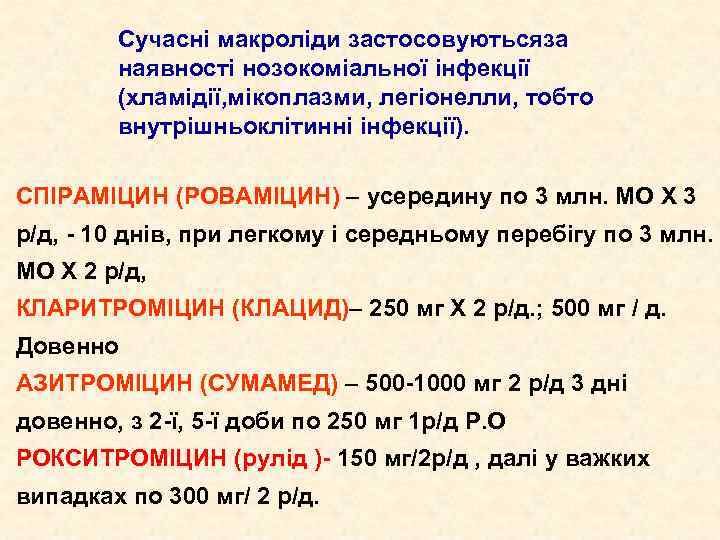

Сучасні макроліди застосовуютьсяза наявності нозокоміальної інфекції (хламідії, мікоплазми, легіонелли, тобто внутрішньоклітинні інфекції). СПІРАМІЦИН (РОВАМІЦИН) – усередину по 3 млн. МО Х 3 р/д, - 10 днів, при легкому і середньому перебігу по 3 млн. МО Х 2 р/д, КЛАРИТРОМІЦИН (КЛАЦИД)– 250 мг Х 2 р/д. ; 500 мг / д. Довенно АЗИТРОМІЦИН (СУМАМЕД) – 500 -1000 мг 2 р/д 3 дні довенно, з 2 -ї, 5 -ї доби по 250 мг 1 р/д Р. О РОКСИТРОМІЦИН (рулід )- 150 мг/2 р/д , далі у важких випадках по 300 мг/ 2 р/д.